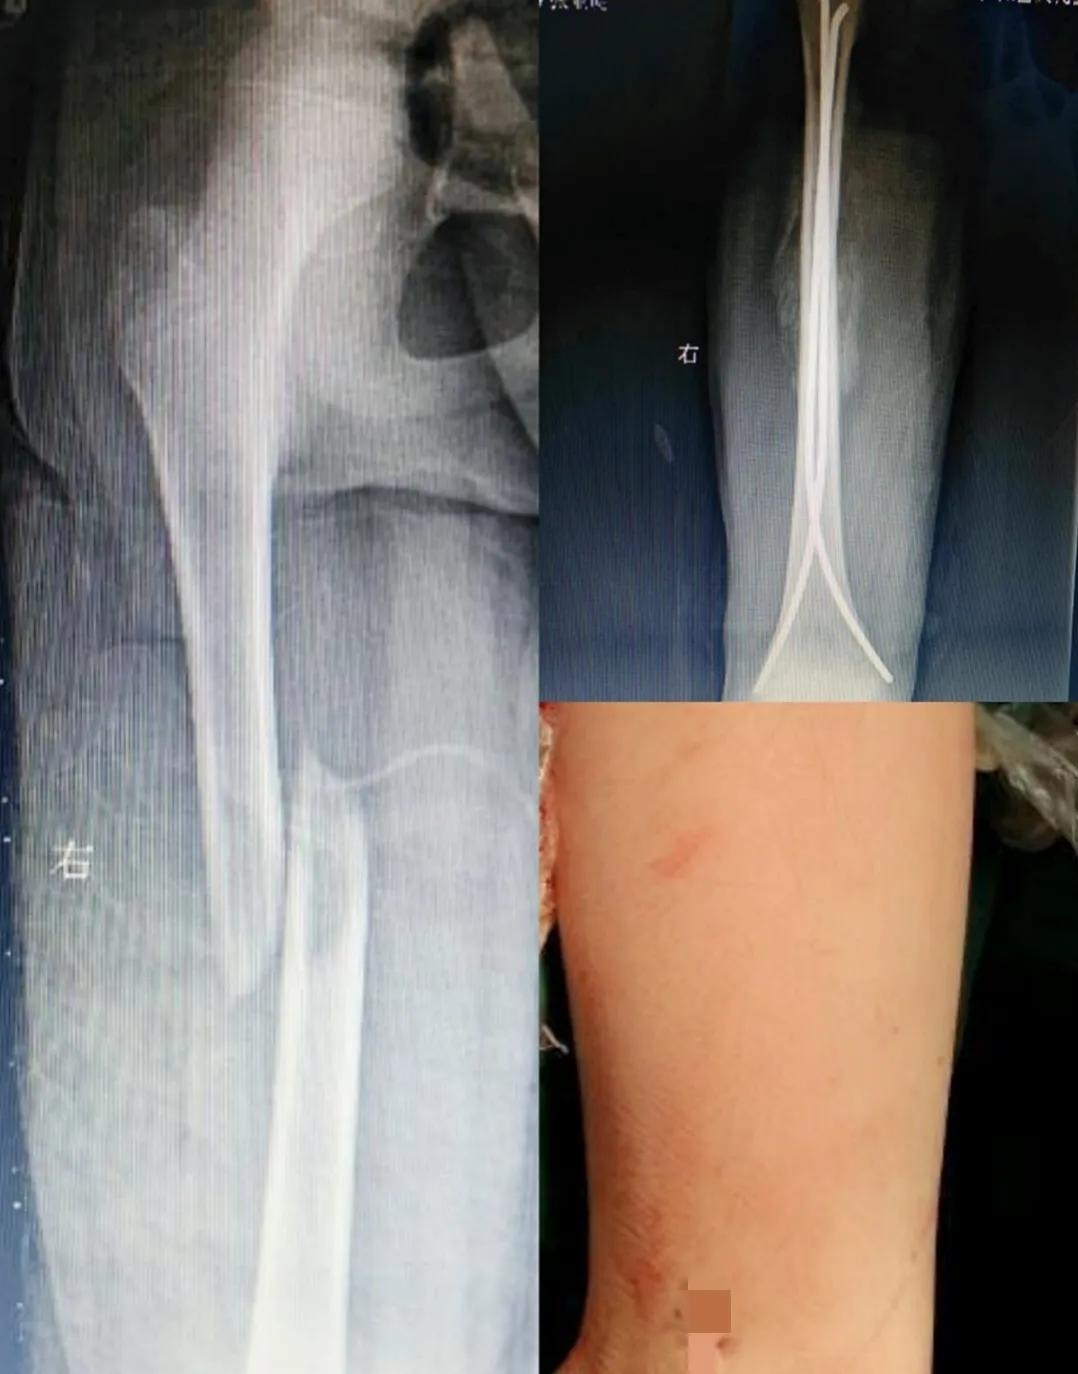

临床上儿童长骨骨折治疗还有一大利器,就是弹性髓内钉。一样可以做到微创。比如下面这个儿童股骨干骨折,只需要2个小口就可以做到微创内固定。